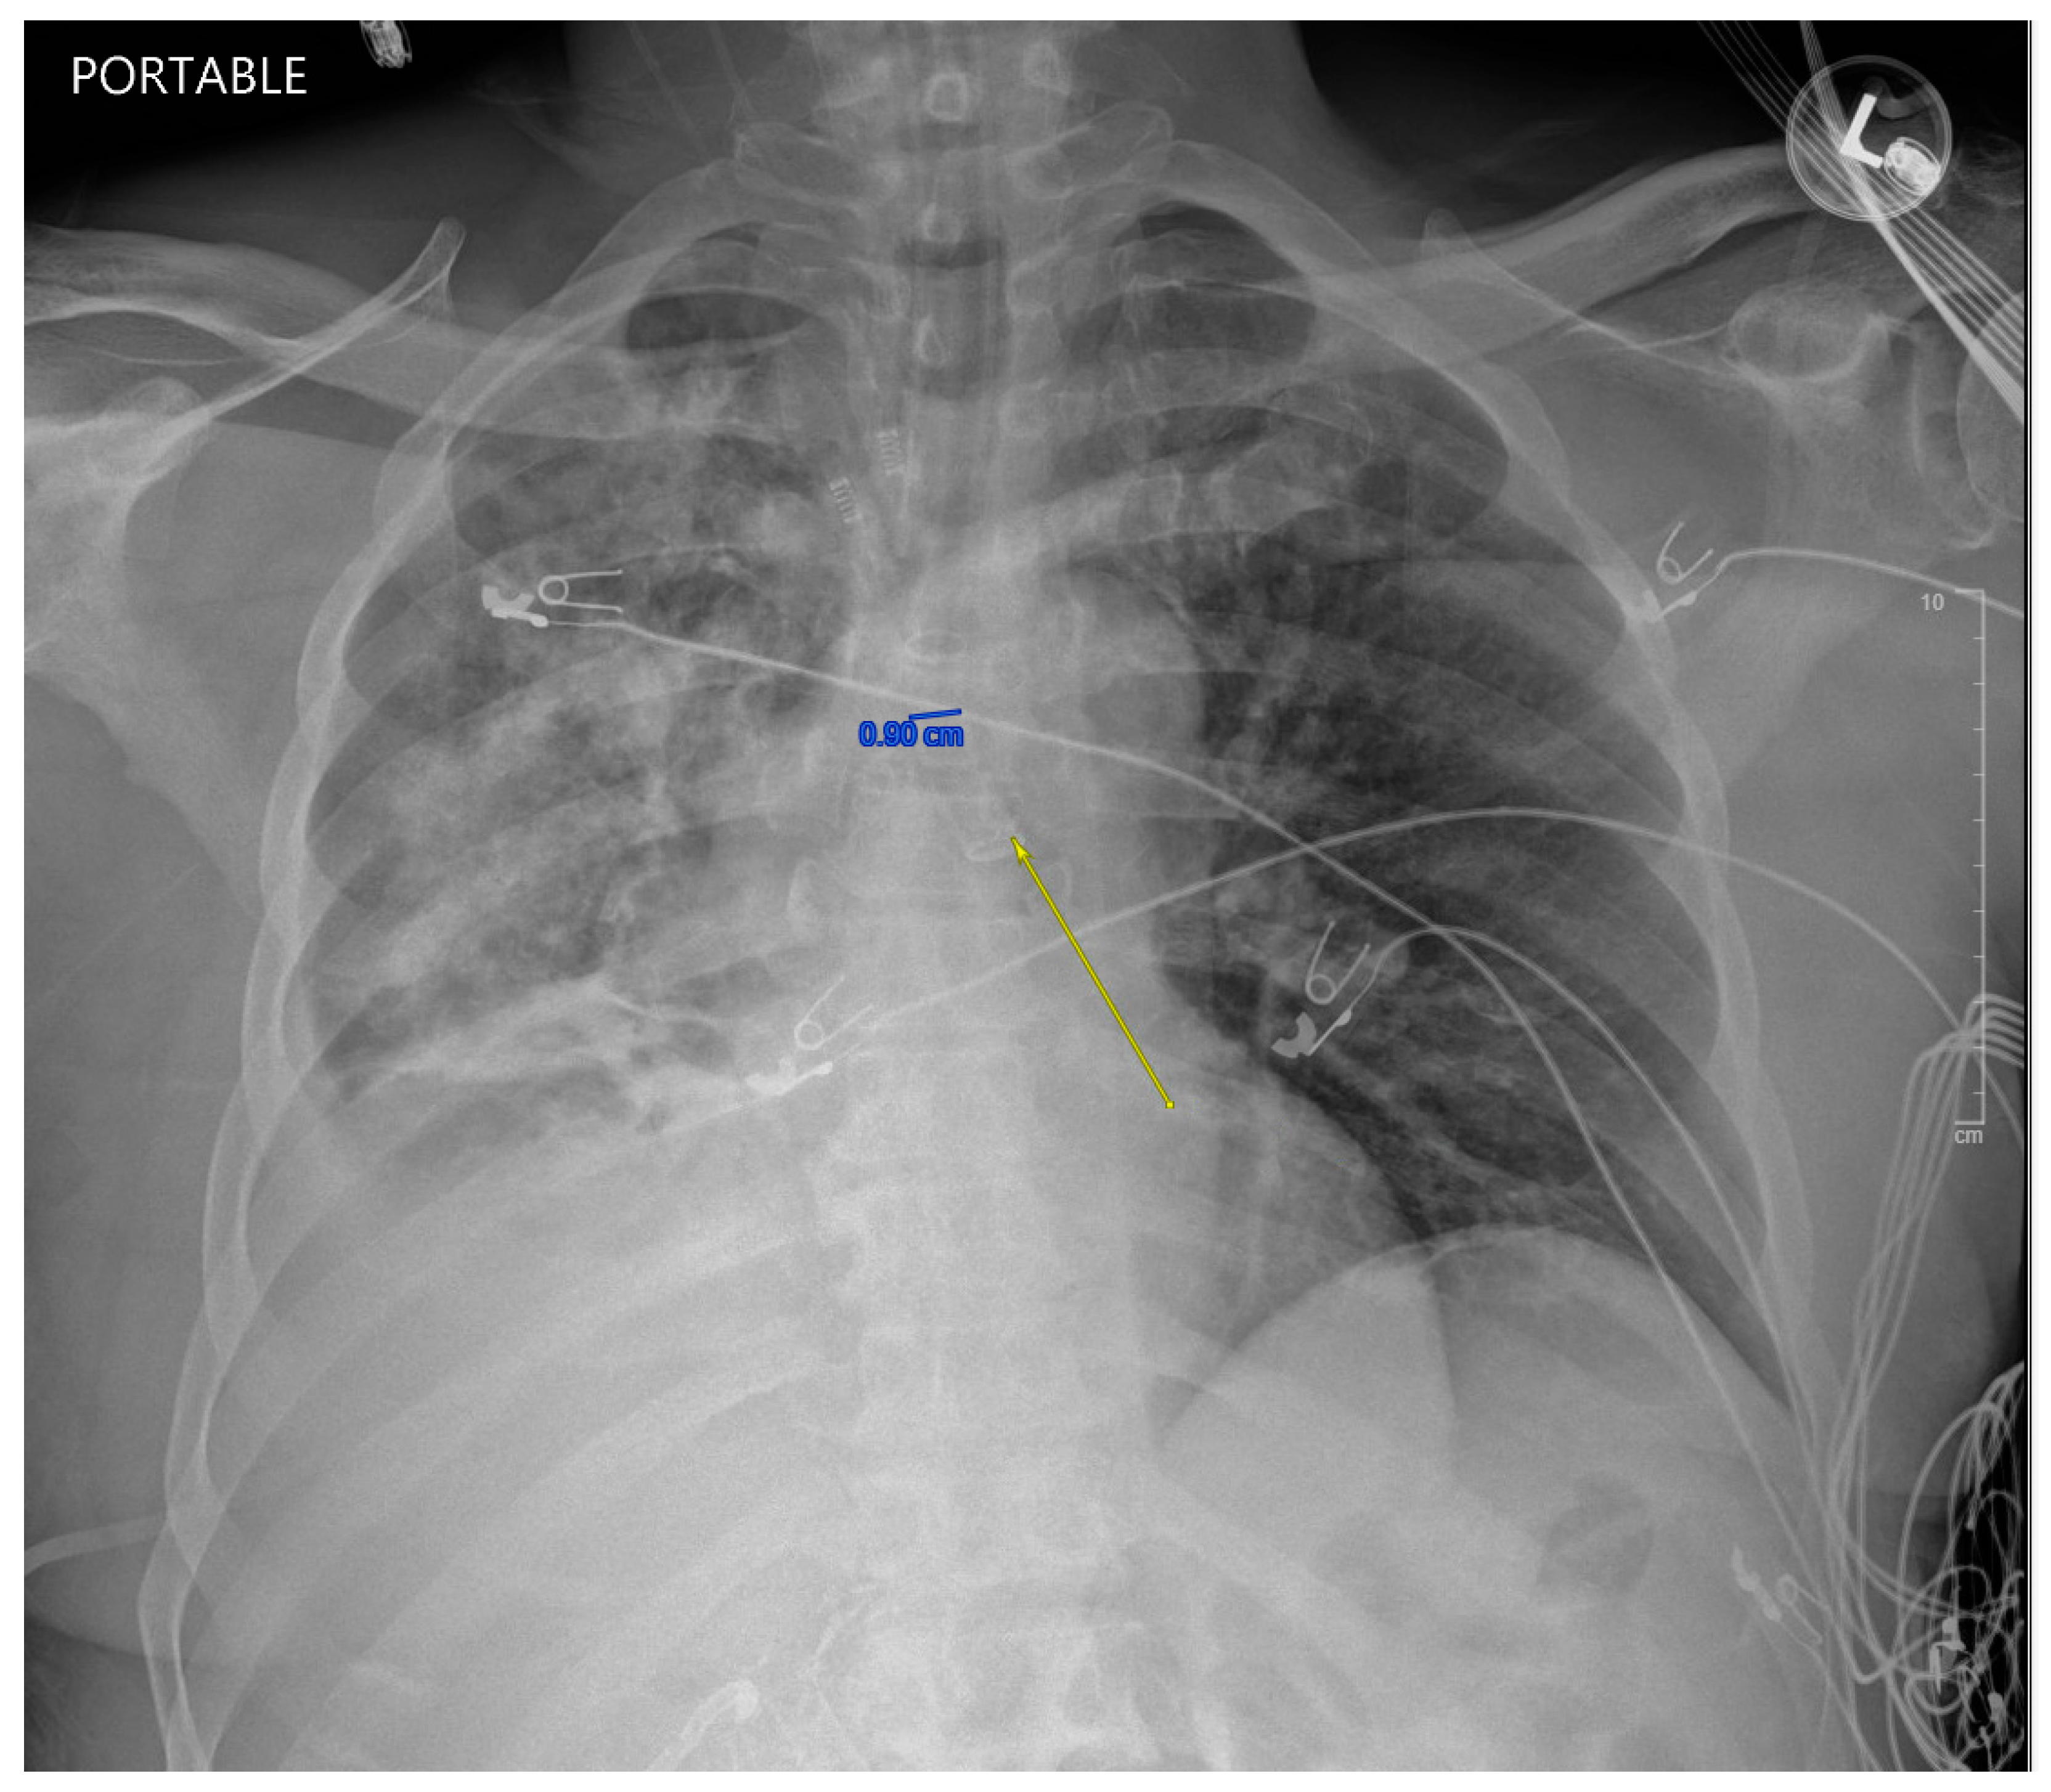

While in the MICU, the patient was weaned off pressors, and IP conducted another bronchoscopy, which showed thick, bloody secretions in the right lower lobe airway. There were no obvious secretions in the left airway. Therapeutic suctioning was performed. The patient remained intubated during post-operative day one and was started on a five-day course of Zosyn given the acute infiltrations seen on chest X-ray in the right lung (see Figure 2). Bile cultures were negative. The patient was extubated on post-operative day two with the difficult airway team present. The patient was alert and oriented to person, place, and time with appropriate biliary drain function (200 cc/day) and ambulating with assistance (ICU mobility level 8). In April 2024, the patient underwent a staging cholangiogram with internalization of the biliary drain (see Figure 3). Finally, the patient underwent a successful embolization of the biliary-pleural fistula in March 2024.

Figure 3. AP interval cholangiogram demonstrating appropriate drainage of the BBF stent. The white arrow demonstrates appropriate drainage through the stent to the external drain.